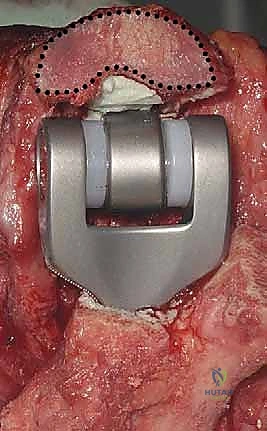

5. تثبيت المفصل النهائي (الإسمنت العظمي)

يتم استخدام المفصل الصناعي النهائي، والذي يتكون غالباً من سبيكة معدنية عالية الجودة (مثل الكوبالت والكروم أو التيتانيوم) مع بطانة من البولي إيثيلين لضمان حركة سلسة. يتم تثبيت جذوع المفصل داخل العظام باستخدام "الإسمنت العظمي الطبي" (Bone Cement) الذي يضمن ثباتاً فورياً وقوياً، وهو أمر حاسم لمرضى هشاشة العظام.

6. ربط المفصل وإغلاق الجرح

بعد جفاف الإسمنت، يتم ربط جزئي المفصل (العضد والزند) معاً بمحور معدني (Linked Prosthesis)، مما يمنع خلع المفصل مستقبلاً. يعيد الدكتور هطيف بناء الأوتار (خاصة وتر العضلة الثلاثية) بدقة متناهية، ثم يتم إغلاق الجرح تجميلياً.